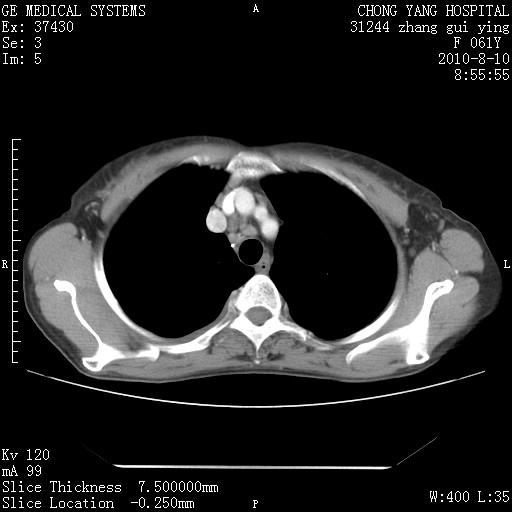

标题: CT28314:F61Y胸部增强,发热咳嗽一周入院,后面的为一周前平 [打印本页]

标题: CT28314:F61Y胸部增强,发热咳嗽一周入院,后面的为一周前平

1、支持考虑右侧中央型肺癌伴右肺中叶节段性不张及下叶支气管黏液痰栓    2、左肺上叶舌段感染。

支持右下肺中央型肺癌并左上肺感染.

支持3楼意见,还要考虑:纵隔及肺门淋巴结转移、右侧少量胸腔积液。

确切的说:1:右肺下叶中心型肺癌侵及中叶支气管并中叶不张,纵膈淋巴结转移。2:左肺舌叶炎症。3:右侧胸腔少量积液

块影平扫32hu,动静脉期62-70hu.

1:右肺下叶中心型肺癌侵及中叶支气管并中叶不张,纵膈淋巴结转移。2:左肺舌叶炎症。3:右侧胸腔少量积液。支持!

右肺下叶中心型肺癌侵及中叶支气管并中叶不张,纵膈淋巴结转移。2:左肺舌叶炎症。3:右侧胸腔少量积液